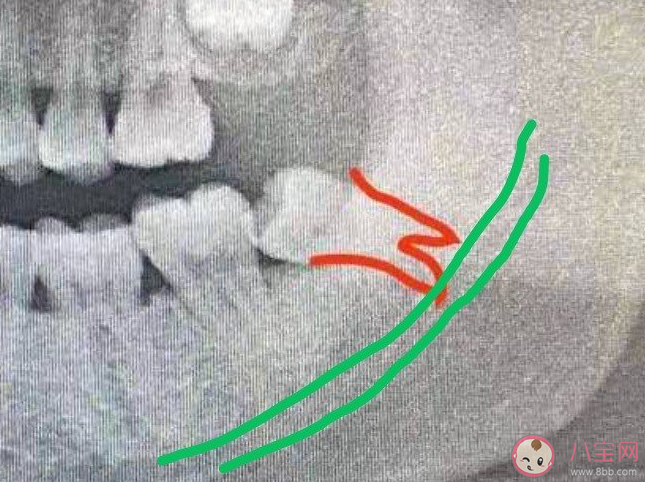

下面这个就没有这么可爱了:

不仅两个牙根是分开的,而且距离下颌神经管很近,这样拔牙难度就增加了许多。医生需要把智齿分成几小块,再一个一个薅出来。

如果牙根不幸折断(通常小于2 mm),又紧邻神经管,为了保护神经,医生有可能就会不再力求全部拿出来,剩余的一点点就会留在骨头里。